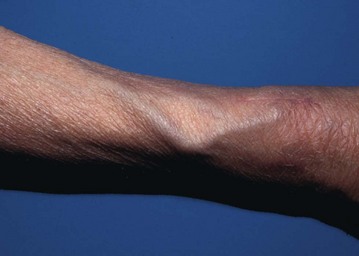

• Odontoid subluxation (Fig. 8.7)—if rheumatoid arthritis involves the atlanto-axial joint, the transverse ligament may be destroyed, allowing the odontoid process to sublux. During general anaesthesia, the protective reflexes are lost. If the neck is hyperextended during intubation, there is a serious risk of injury to the spinal cord by the unrestrained odontoid

Full blood count is essential to check for non-specific anaemia or iron deficiency anaemia; and plasma urea, electrolytes and creatinine are measured to identify chronic or drug-induced disturbance of renal function; inflammatory markers (ESR and CRP) indicate the activity of the disease. Preoperative assessment must include clinical examination of neck movements and cervical spine X-rays.